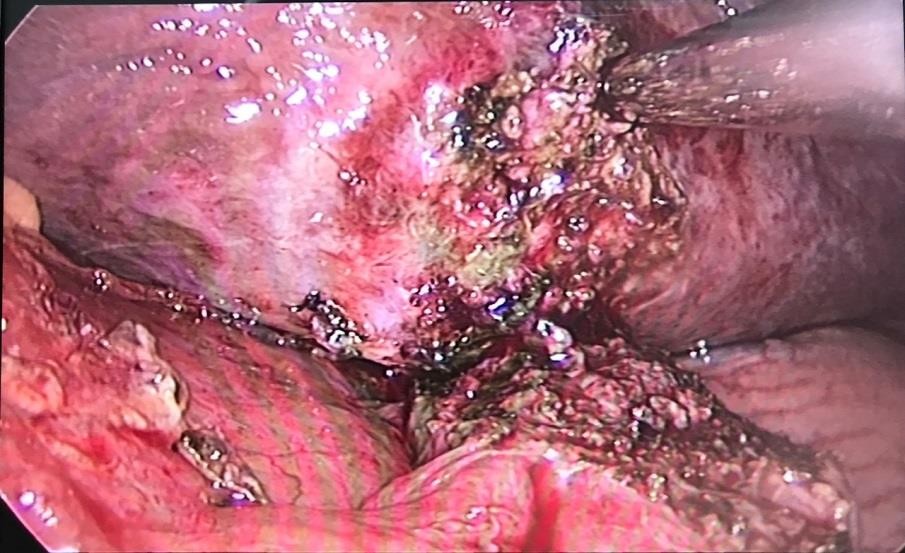

Một số hình ảnh ghi nhận trong và sau mổ:

Hình 2: Khối viêm dính mặt dưới gan trái, mạc nối nhỏ và thân tụy

Hình 3. Khối viêm dính được tiến hành phẫu tích